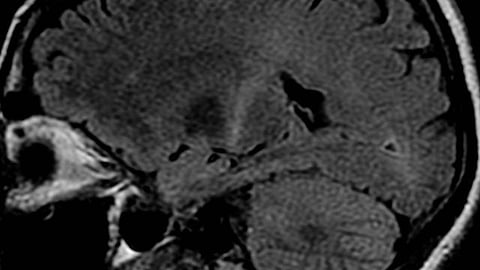

ALS is a degenerative disease of the nervous system particularly affecting and harmful to motor neurons. As the disease progresses, the nerve cells controlling voluntary muscle movement die. That leads to a progressive wasting of the muscles responsible for moving and speaking, but also for eating and breathing. To date, says Prof. Bading, there is no effective drug treatment for ALS patients, who in most cases die within two to five years after the diagnosis.

The neuroprotective molecule FP802 binds to the TwinF protein pocket of TRPM4, blocks the contact areas of the interacting proteins, and thereby disrupts the fatal complex of NMDA receptors and TRPM4. The Heidelberg scientists have studied this new drug principle using an ALS mouse model as well as brain organoids of ALS patients. “With this completely new therapeutic concept in combating neurodegenerative diseases we were able to achieve remarkable outcomes,” says Prof. Bading.